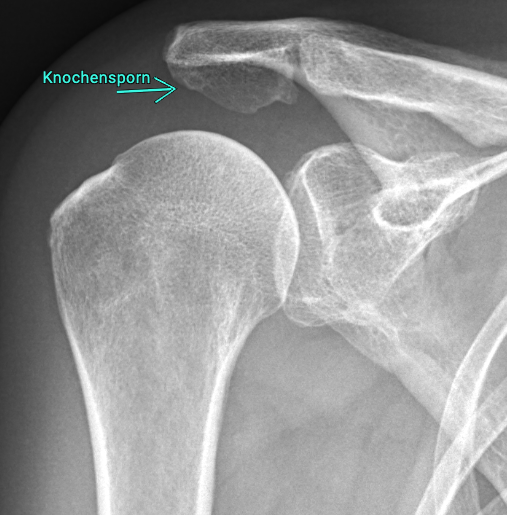

Tightness syndrome, also known as impingement syndrome, is one of the most common causes of shoulder pain. It is a mechanical tightness in the shoulder joint in which the rotator cuff tendons and the bursa are trapped between the humeral head and the acromion. Often caused by an imbalance or lack of centering of the humeral head in the glenoid cavity, sometimes also by a bone spur on the acromion

This friction leads to pain, especially during overhead movements or when lifting the arm sideways.